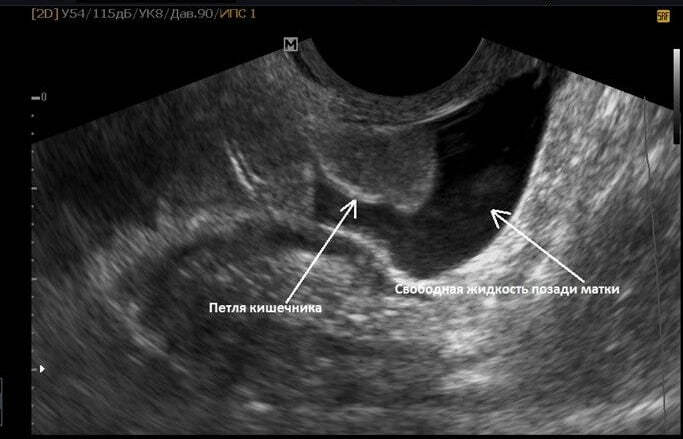

Жидкость в малом тазу за маткой – проблема, которую часто выявляют при проведении ультразвукового исследования у женщин. В отдельных случаях в гинекологии это является нормой, но также может указывать на патологию – внутреннее кровотечение или воспалительные процессы. Все зависит от объемов выявленного выпота в матке или позадиматочном (дугласовом) пространстве. Конкретную причину появления экссудата можно выявить только при комплексном обследовании.

Определить по эхограмме, какой именно тип жидкости обнаружен в малом тазу у женщины невозможно. Однако доктор, который проводит исследование может выдвинуть некоторые предположения. Они будут основаны на сопутствующих показаниях. Для уточнения данного вопроса потребуется диагностика.

Скопление жидкости в малом тазу, которую определяют при проведении эхографии (ультразвукового исследования) может проявляться у женщин по разному. Ввиду того, что данная проблема скорее является следствием, а не самой патологией, клиническая картина будет меняться, в зависимости от причин. Из общих симптомов жидкости в малом тазу можно выделить:

Свободная жидкость локализованная в малом тазу на УЗИ, может указывать на внематочную беременность. Такую патологию диагностируют на фоне целого симптомокомплекса:

Когда объемы обнаруженной водянки до 50 мл, то это указывает на наличие воспалительного процесса или каких-то факторов, препятствующих нормальному оттоку воды. Если жидкости в области органов малого таза большое количество, то необходима экстренная помощь, которую окажут после полноценного обследования.